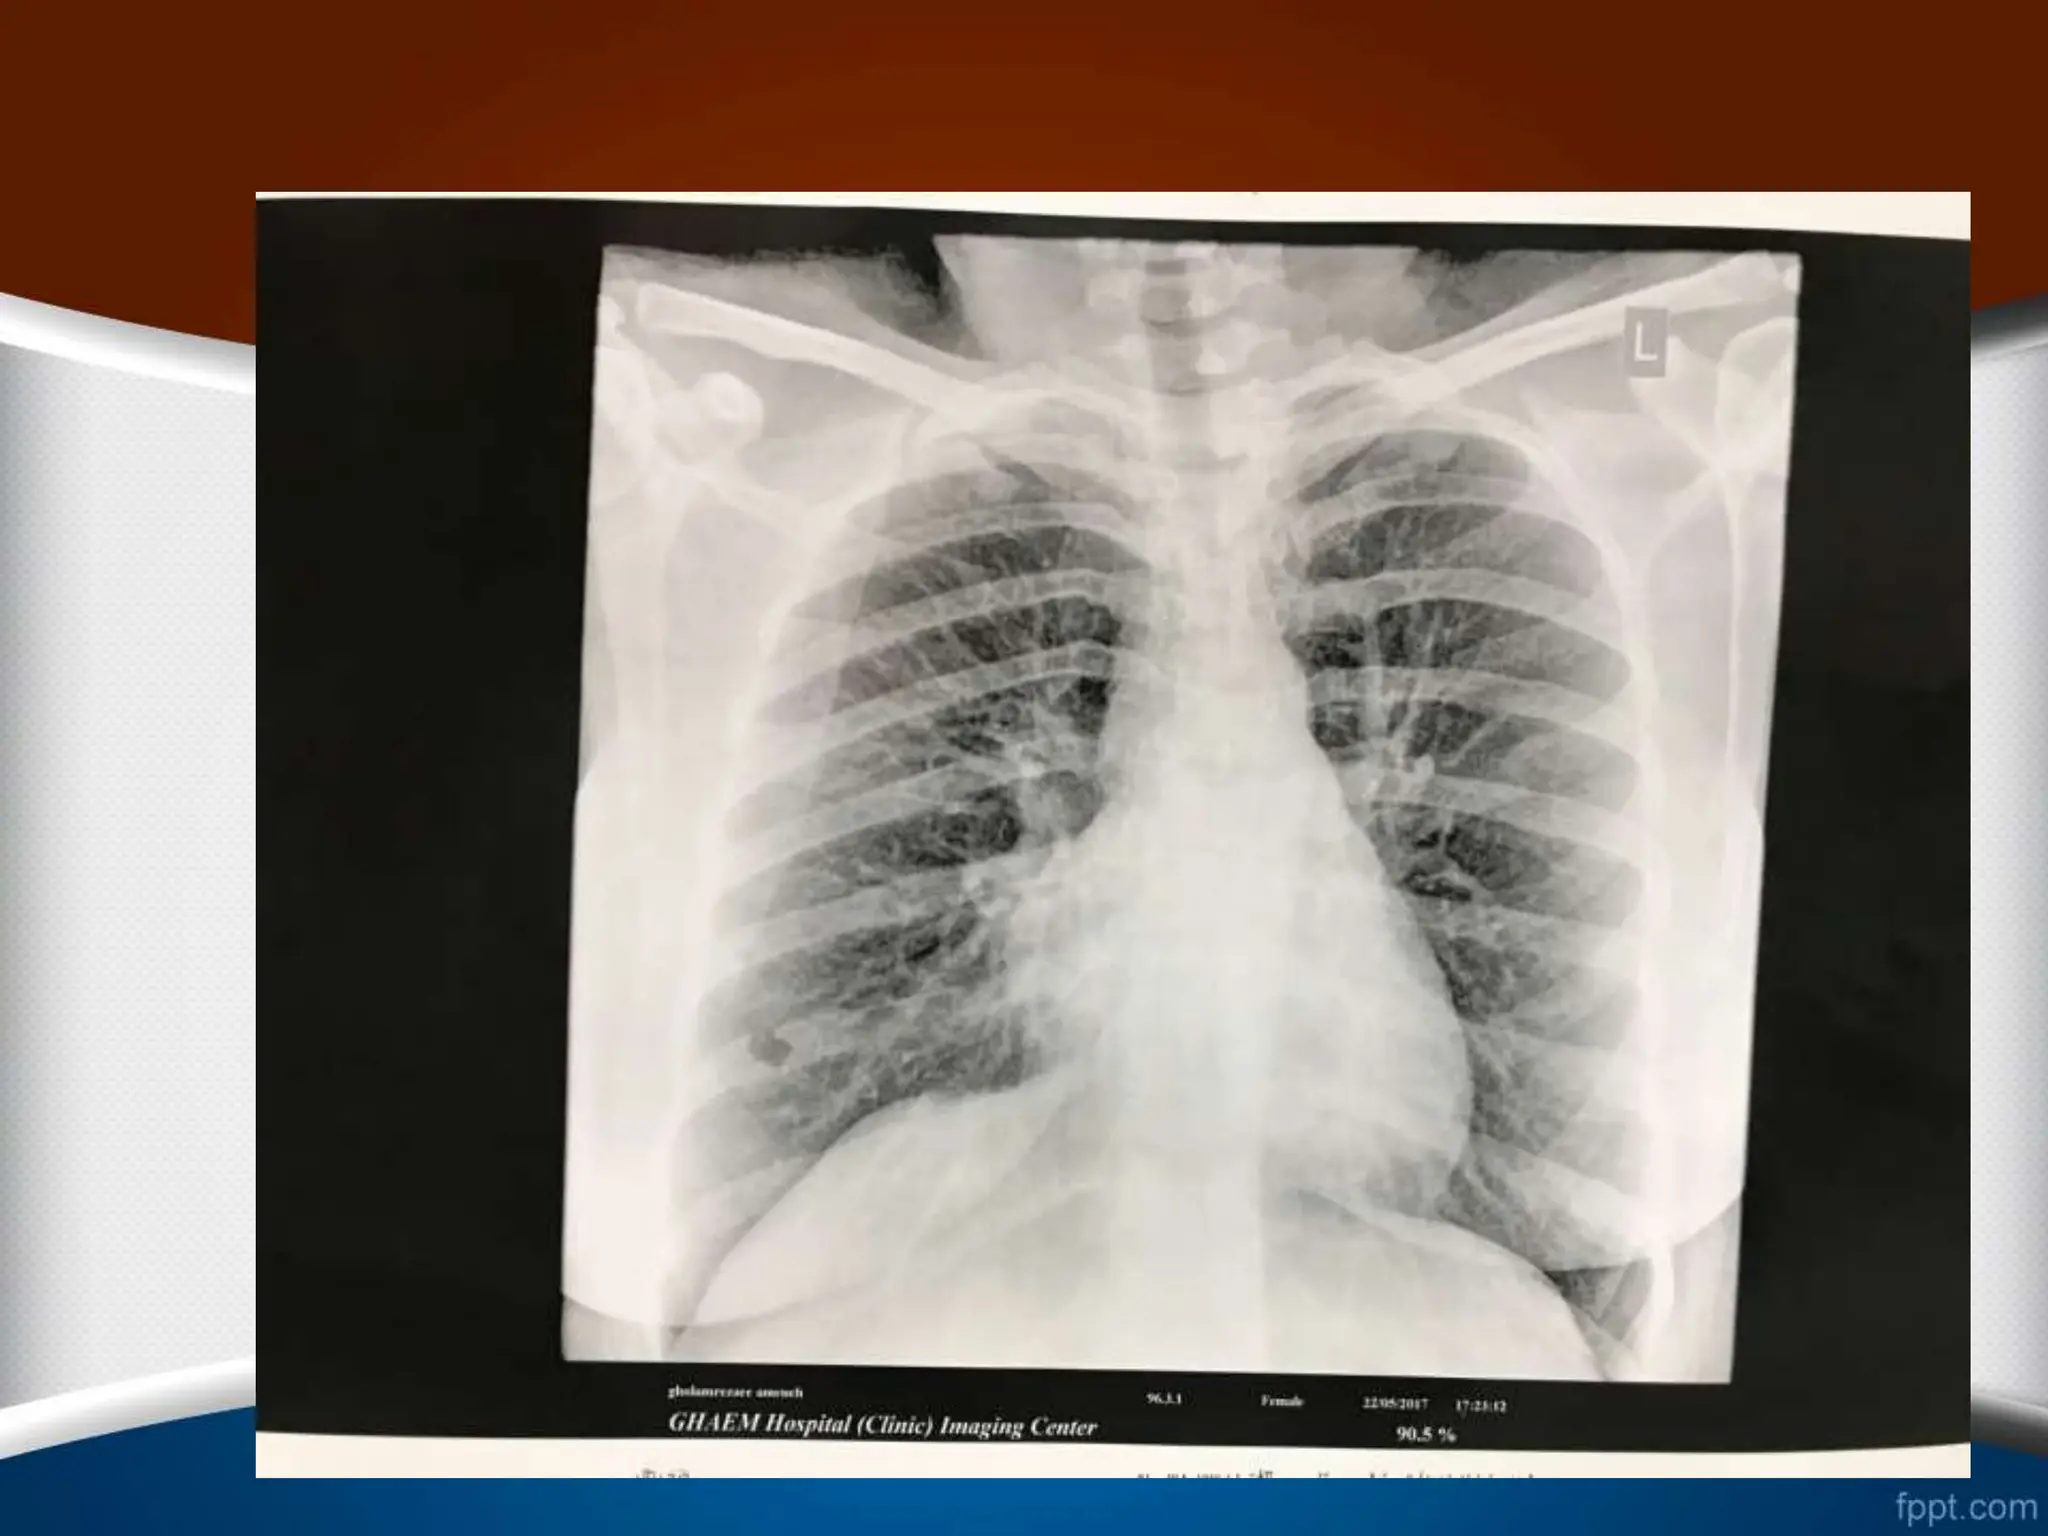

‫ریوی‬ ‫عروق‬ ‫طرح‬

1

.

‫نرمال‬

2

Pulmonary Venous Hypertension

(Post Capillary Pulmonary

Hypertension)

‫ریوی‬ ‫عروق‬ ‫بررسی‬ ‫پارامترهای‬

.1

‫پولمونر‬ ‫راست‬ ‫نزولی‬ ‫شریان‬ ‫گیری‬ ‫اندازه‬

.2

‫محیط‬ ‫به‬ ‫مرکز‬ ‫از‬ ‫ریه‬ ‫عروق‬ ‫طرح‬ ‫انتشار‬

.3

‫قاعده‬ ‫طرف‬ ‫به‬ ‫قله‬ ‫از‬ ‫آن‬ ‫انتشار‬

‫ریوی‬ ‫عروق‬ ‫نرمال‬ ‫طرح‬

RDPA

‫از‬ ‫کمتر‬ ‫نرمال‬ ‫خانم‬ ‫فرد‬ ‫در‬

16

‫آقای‬ ‫در‬ ‫و‬ ‫متر‬ ‫میلی‬

‫از‬ ‫کمتر‬ ‫نرمال‬

18

‫متر‬ ‫میلی‬

‫در‬

1/3

‫رادیوگرافی‬ ‫در‬ ‫نرمال‬ ‫فرد‬ ‫یک‬ ‫در‬ ‫ریه‬ ‫محیط‬

PA

‫طرح‬

‫شود‬ ‫نمی‬ ‫دیده‬ ‫عروقی‬

‫شریان‬ ‫سایز‬ ‫نسبت‬

(

A

)

‫برونش‬ ‫به‬

B

‫یعنی‬

A/B

‫ریه‬ ‫قله‬ ‫در‬

‫های‬

85

%

‫نسبت‬ ‫این‬ ‫ریه‬ ‫ی‬ ‫قاعده‬ ‫در‬ ‫و‬ ‫یک‬ ‫ریه‬ ‫ناف‬ ‫در‬ ‫و‬

35/1

‫است‬